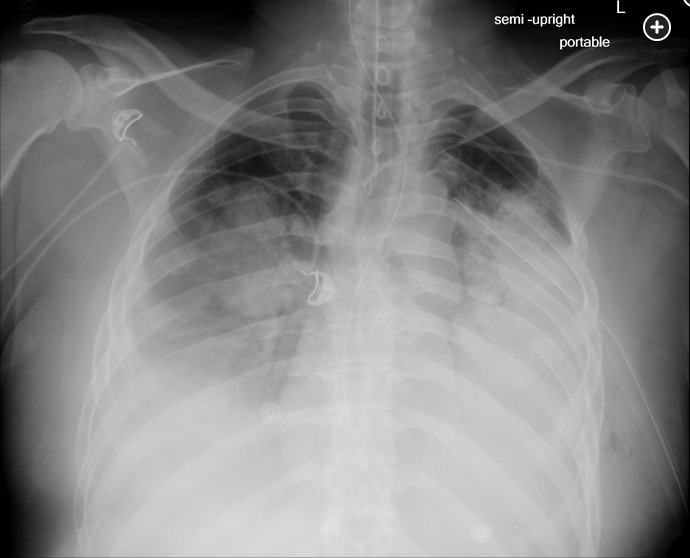

A 44-year-old man was kicked in the chest during an altercation 2 months ago and has had persistent left anterolateral chest wall pain and shortness of breath. He has had no fever or chills. His presenting chest radiograph today is shown (Figure 1). Following tube thoracostomy, 2 L of bloody pleural fluid are removed, and a second chest radiograph is obtained (Figure 2). The hematocrit of the pleural fluid is 10%, while the peripheral blood hematocrit is 43%. The pleural fluid has a pH of 7.15, WBC count of 7,200/μL (7.20 × 109/L), and lactate dehydrogenase of 1,533 U/L (25.60 µkat/L). Gram stain shows no organisms. Over the next 4 h, his shortness of breath worsens. His SpO2 is now 70% on 50% oxygen via face mask. Following emergent intubation, a repeat chest radiograph is obtained (Figure 3). The most likely explanation for this patient’s clinical deterioration is which of the following?

The 2-month history of this patient’s lung collapse places him at increased risk for reexpansion pulmonary edema. In patients with chronic collapse of a lobe or whole lung, rapid reexpansion can abruptly increase pulmonary blood flow, leading to stress capillary failure on the affected side. This endothelial injury leads to the recruitment and activation of inflammatory cells and the release proinflammatory cytokines that can increase the permeability in both the affected lung and in the contralateral lung.123